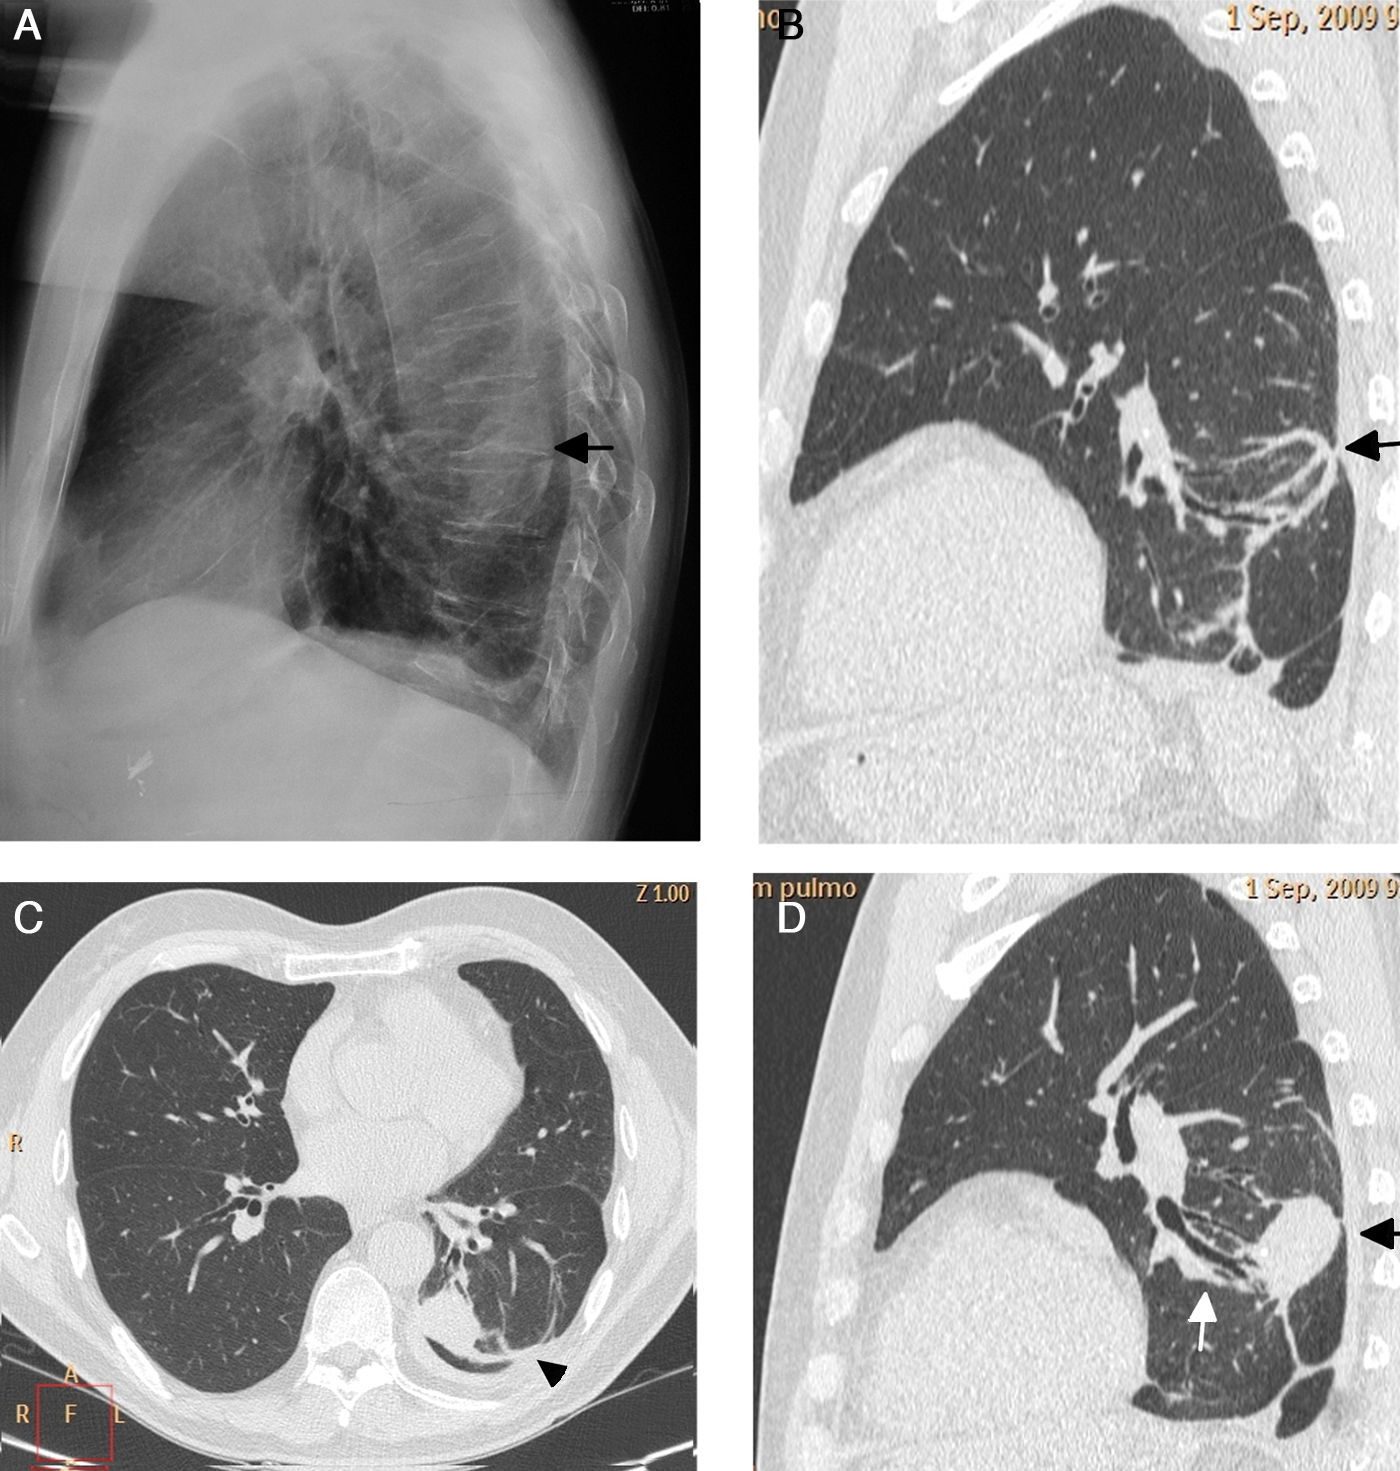

La atelectasia pulmonar es un indicador importante de una enfermedad subyacente, potencialmente grave, que es imprescindible diagnosticar precozmente. Uno de los mecanismos más frecuentes es la reabsorción de aire distal a la obstrucción de las vías respiratorias. La radiografía de tórax es una herramienta excelente para diagnosticarla, especialmente útil para descartar obstrucciones bronquiales centrales (por ejemplo, una neoplasia endobronquial). Si no se reconocen correctamente los signos de la pérdida de volumen el diagnóstico y el tratamiento pueden retrasarse. En este artículo se describen los principales hallazgos radiográficos de la atelectasia pulmonar lobular y su correlación con la tomografía computarizada. Se incluyen los signos clásicos descritos en la bibliografía y otros menos conocidos y a su vez sutiles.

Atelectasis is an important indicator of potentially severe underlying disease that must be diagnosed as early as possible. One of the most common mechanisms is the reabsorption of air distal to respiratory tract obstruction. The chest X-ray is an excellent tool to diagnose atelectasis, and it is especially useful for ruling out central bronchial obstructions (e.g., from endobronchial tumors). If the signs of volume loss are not recognized correctly, the diagnosis and treatment can be delayed. This article describes the main findings of lobar atelectasis on chest X-rays and their correlations with CT findings, including the classic signs described in the literature and other, less known and sometimes subtle signs.